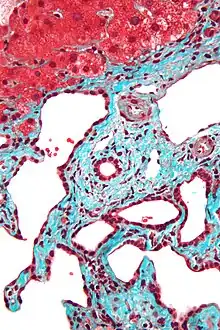

Low magnification micrograph of a bile duct hamartoma. Trichrome stain.

Micrograph of a bile duct hamartoma. Trichrome stain. Intermediate magnification

Micrograph of a bile duct hamartoma. Trichrome stain, high magnification